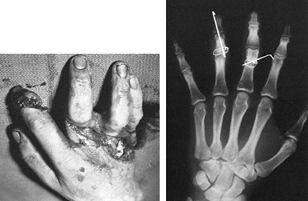

![]() |

|

Figure 40.15.

A 19-year-old right-hand-dominant student caught his right hand in a table saw. Extensive soft-tissue and skeletal disruption resulted. The phalangeal fractures in the long and ring figers were fixed with an interosseous wire as well as an additional Kirschner wire for rotational control. Revascularization of the involved digits was also required. |